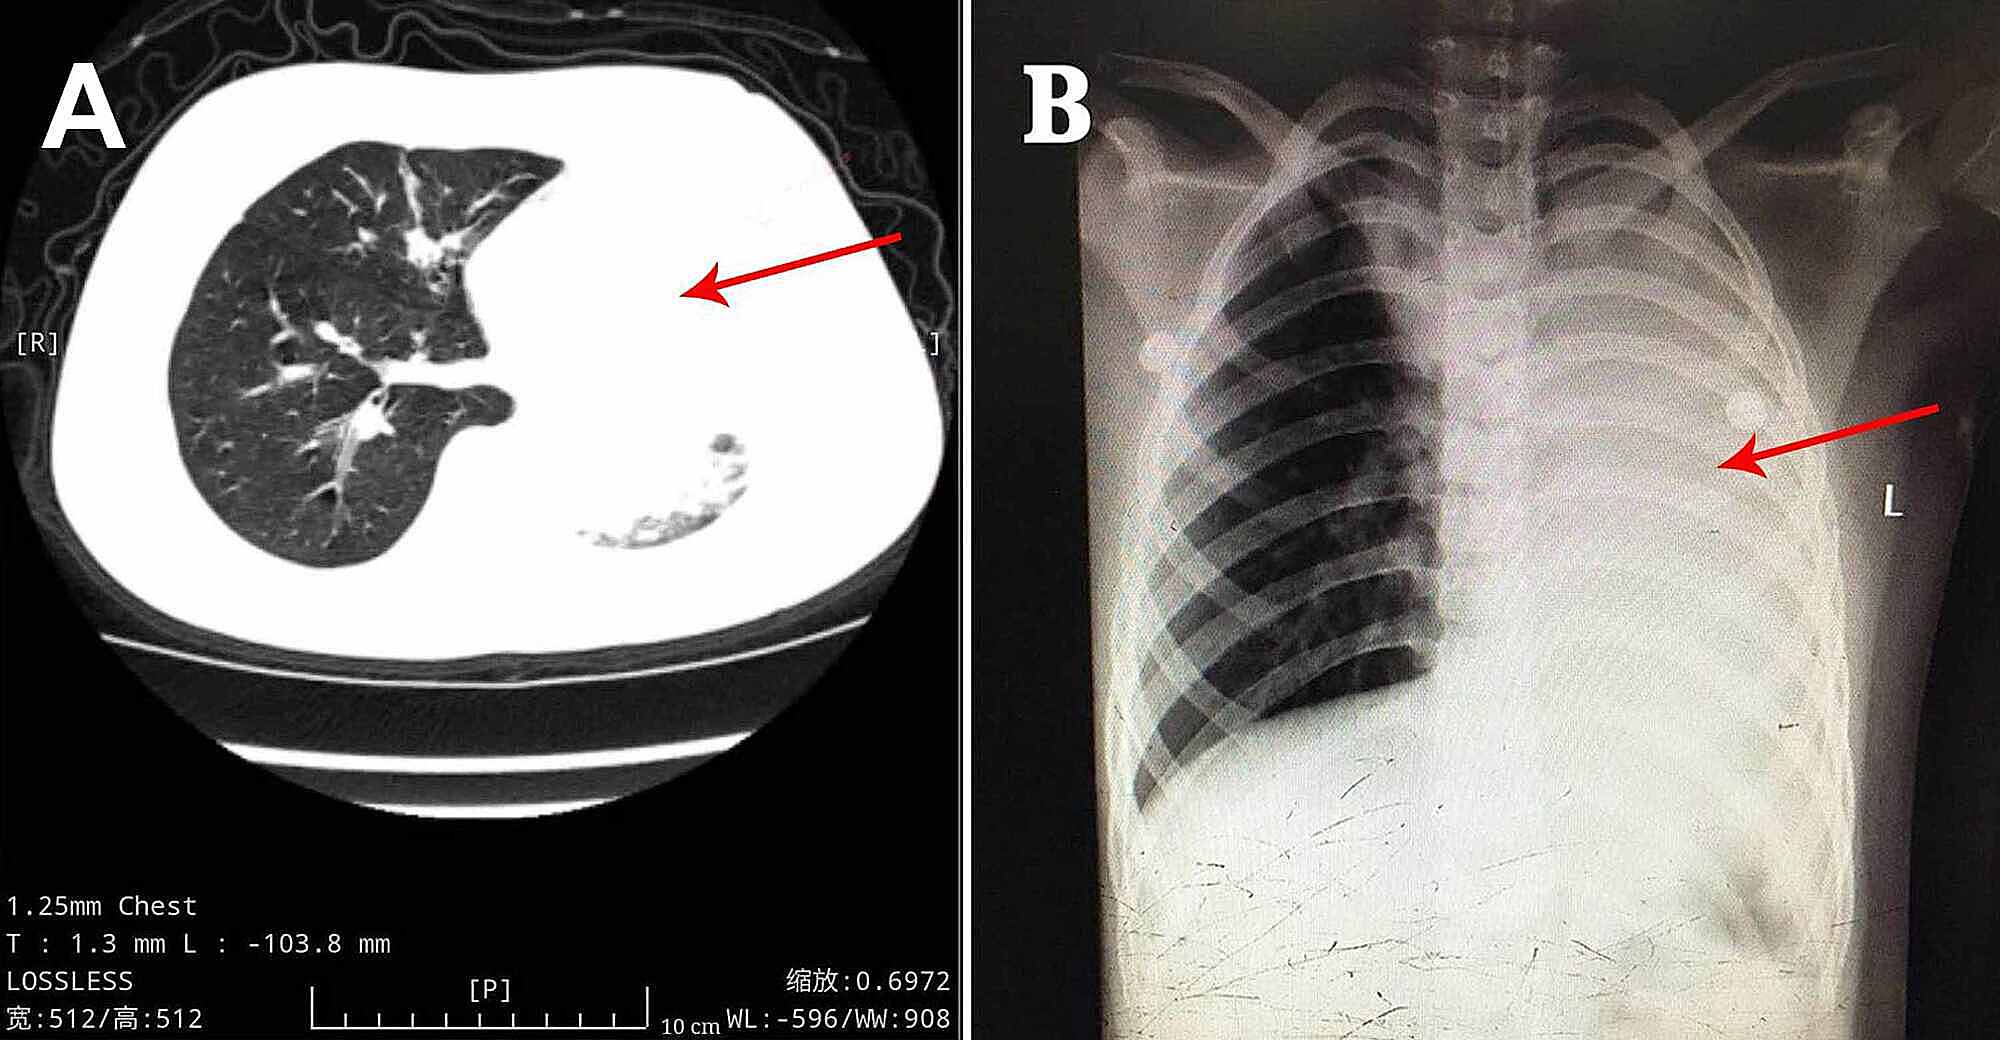

A previously healthy eight-year-old boy, without the history of wheezing and foreign body inhalation, was transferred to the emergency center of Jiangxi Provincial Children's Hospital from a basic-level hospital with a two-day history of fever, cough, and progressive dyspnea. His body temperature was approximately 38 °C. He had been previously treated with antibiotics at a local hospital without improvement except the normalized body temperature. Subsequently, he underwent chest computed tomography (CT) scans, which revealed atelectasis in the left lung and a foreign body in the left upper bronchus, along with pneumonia in the right lung (Figure 1A). In our emergency department, physical examination showed clouding of consciousness, cyanosis, rales, and diminished breath sounds in both lungs. Other parameters were as follows: body temperature, 36.9 °C; heart rate, 150 beats/minute; respiratory rate, 46 breaths/minutes; percutaneous oxygen saturation, approximately 70% under high-flow oxygen therapy. Since the local chest CT scan and clinical manifestations indicated a high possibility of foreign body inhalation, urgent bronchoscopy was performed. This procedure did not reveal the presence of any foreign body in the trachea of this patient but showed the presence of white gelatinous secretions that completely blocked the left main bronchus. Upon removal, it was observed that the secretions are shaped like a bronchial tree (Figure 2A). However, after this cast removal followed by bronchial lavage, there was no significant improvement in oxygen saturation, which fluctuated between 70% and 80%. The patient was admitted to the pediatric intensive care unit and intubated immediately.

After the observation of the cast that was removed via bronchoscopy, PB diagnosis was confirmed. Further, histopathology indicated that the casts predominantly comprised of inflammatory necrotic tissue, mucin, numerous neutrophils, and eosinophils (Figure 2C). Chest X-ray revealed pneumonia in both lung lobes and atelectasis in the left lung (Figure 1B), suggesting airway blockage by residual casts. Furthermore, complete blood count revealed the following: white blood cells, 13.11×109 cells/L (leukocytosis); neutrophils, 85.4%; hemoglobin, 145 g/L; and platelets, 350×1012/L. The blood biochemistry results of this patient were as follows: C-reactive protein (CRP), 42.6 mg/L; IgE, 908.4 IU/ml; IgA, 1.04 IU/ml; IgM, 0.62 IU/ml; and IgG, 12.15 IU/ml. As PB diagnosis is confirmed, along with extensive inflammatory necrotic tissue in the casts, we started treatments as follows: imipenem-cilastatin sodium (30 mg/kg, q6h) for anti-infection; azithromycin (10 mg/kg, qd); intravenous methylprednisolone (1 mg/kg, q12h); nebulized dexamethasone (5 mg, q6h) for anti-inflammation; nebulized bronchodilators, intensive chest physiotherapy, and intravenous mucosolvan for mucolytic therapy. However, oxygen saturation still fluctuated at approximately 80% without improvement for the next two days. Sputum etiology examination was positive for influenza A virus and negative for other viruses and Mycoplasma pneumoniae RNA, as well as fungi and bacteria. Additionally, blood cultures for bacteria and fungi were also negative.

Treatment regimens were adjusted based on the etiological results. Imipenem-cilastatin sodium and vancomycin were discontinued; further, the patient was administered with piperacillin (50 mg/kg, bid), and added Oseltamivir for anti-influenza A virus. Azithromycin (10 mg/kg, qd), intravenous methylprednisolone (1 mg/kg, q12h), nebulized dexamethasone (5 mg, q6h), nebulized bronchodilators, intensive chest physiotherapy, and intravenous mucosolvan were continued. However, there was still no improvement. Considering the histopathology showed the casts predominantly comprised of mucin, and the mucolytic agent mucosolvan, as well as bronchodilators, were not effective, we used a mucolytic agent-α-chymotrypsin, which has been reported to liquefy the mucus. α-chymotrypsin (2000 IU, 5 mL saline) was intratracheally instilled twice a day via the endotracheal tube, supplemented by frequent intratracheal suction and chest physiotherapy. Consequently, abundant purulent secretions and casts were discharged (Figure 2B); further, the oxygen saturation increased to 93% and there were enhanced breath sounds in both lungs. The patient was successfully extubated with gradual improvement in his condition. Subsequently, the patient received oral azithromycin (10 mg/kg, three times per week) and nebulized budesonide (1 mg added in 2 mL saline, twice daily). Chest CT reexamination showed the full expansion of the left lung with pleural effusion on the left thorax and bilateral pneumonia (Figure 3A). Additionally, fiberoptic bronchoscopy revealed endobronchial intima infection without casts (Figure 4). After six days, he was discharged with a little cough and no neurological sequelae; continued on oral azithromycin and nebulized budesonide treatment for two weeks. The timeline of this case was shown in Figure 5. During the next four follow-up visits, the patient was asymptomatic and without recurrent casts. Further, his chest CT scan showed increased lung markings (Figure 3B).